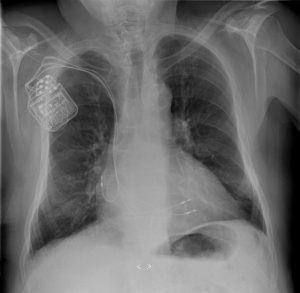

Last year researchers from the University of Leuven in Belgium and the University of Birmingham in the UK found a way to hack into implanted medical devices. Intercepting signals between pacemakers and their programmers, they were able to steal medical information, drain the device’s battery, and even send malicious messages, causing the devices to malfunction and disrupt critical lifesaving care.

This problem is not isolated. Implanted devices often connect to sensors and monitors within a hospital without using passwords, encryption or other security measures. Wireless connectivity and remote monitoring make it easier for health providers to adjust device settings without invasive procedures, but they also create a potential ‘back-door’ into hospital networks. Unsecured devices can provide hackers with an entry point to steal valuable medical data or launch a widespread ransomware attack.

After being hit by recent discoveries of security flaws in on-the-market insulin pumps, pacemakers, and infusion pumps, cyber security researchers and medical suppliers are even considering a “Hippocratic oath” for device makers who, like doctors, would vow to act in the best interest of patients. There has also been an increase in regulatory action, with the FDA now requiring a firmware update intended to reduce the risk of a certain type of cardiac pacemaker being hacked.